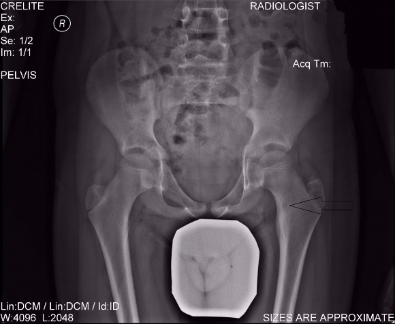

Οι εικόνες απεικονίζουν ένα περιστατικό με την Νόσο του Όλιερ, όπου παρουσίαζε κοντύτερο αριστερό άκρο. Χειρουργήθηκε από τον Δρ. Ζένιο με την χρήση εξωτερικής οστεοσύνθεσης.

Προ-εγχειρητικά

Εξωτερική οστεοσύνθεση

Μετ-εγχειρητικά